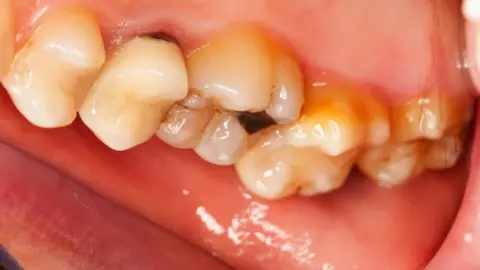

Getty ImagesTooth erosion - the facts

- It is progressive loss of the hard substance of a tooth by chemical processes that do not involve bacterial action

- The acidity of the food or drinks is critical rather than the sugar content (bacteria, along with sugar, cause tooth decay not erosion)

- Diet, lifestyle choices, the environment and in some cases medication can increase the risk

- Using fluoride toothpastes or rinses and modifying your diet can reduce the risk of erosion